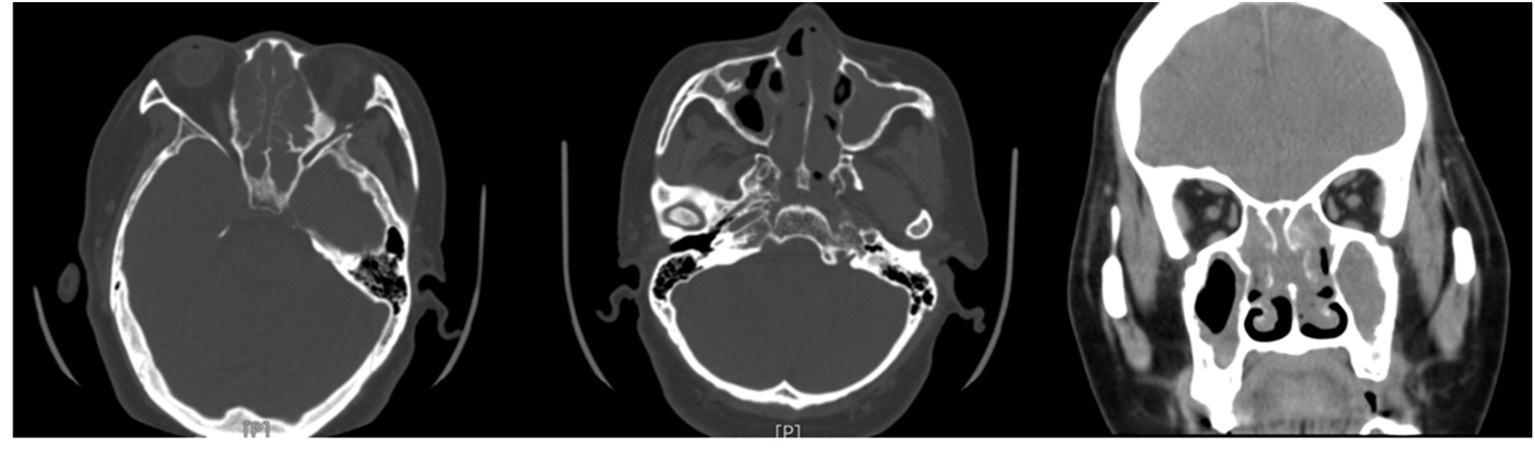

4) 术前检查示:2025-10-28入院副鼻窦CT:1) 全组副鼻窦炎,真菌感染不除外,请结合临床,2) 双侧中上鼻甲观察不清,鼻腔内软组织密度影,分泌物?其他?请结合内镜检查(见图1);2025-10-28术前鼻内镜检查:鼻息肉;鼻窦炎,请结合CT (见图2)。2025-10-28血细胞分析:嗜酸性粒细胞百分比11.90 (%) ↑,嗜碱性粒细胞百分比1.50 (%) ↑,单核细胞0.61 (109/L) ↑,嗜酸性粒细胞1.12 (109/L) ↑,嗜碱性粒细胞0.14 (109/L) ↑,红细胞5.56 (1012/L) ↑,血红蛋白151 (g/L) ↑,红细胞压积0.46 (L/L) ↑,血小板356 (109/L) ↑,血小板分布宽度8.70 (fL) ↓:2025-10-28尿液干化学检测:维生素C + T,白细胞酯酶++ ↑:2025-10-28血脂四项,肾功三项,血糖,心肌酶谱(5项),肝功(11项),电解质五项:胆固醇6.54 (mmo1/L) ↑,甘油三酯4.49 (mmo1/L) ↑,低密度脂蛋白胆固醇4.36 (mmol/L) ↑,葡萄糖8.78 (mmol1/L) ↑,钙2.57 (mmo1/L) ↑;2025-10-28心电图示:1) 窦性心律不齐,HR:85次/分,2) 部分导联ST段改变;2025-10-29早餐后2 h血糖5.9 mmo1/L,2025-10-28心脏彩超 + 组织多普勒显像 + 左心功能测定 + 室壁运动分析,主动脉瓣少量反流。2025-10-28胸部正位,1) 心、肺、膈未见明显异常,2) 胸椎内固定表现。

Figure 1. Sinus CT scan

1. 副鼻窦CT

指南指出(2024) [5],DTRS因其复杂的发病机制导致患者病情缠绵难愈;对临床常用治疗抗生素和糖皮质激素抵抗;异常的鼻腔结构的形成:骨质异常增生、引流通道的阻塞以及鼻腔、鼻窦黏膜持续性的炎症[10]——嗜酸及中性粒细胞升高等共同导致DTRS的形成。部分研究表明,鼻息肉及外周血嗜酸性粒细胞是导致DTRS的高危因素[11],但关于鼻息肉的成因尚未达成共识,但有研究表明高达38%~69% CRS术后复发是由鼻息肉导致的[12]-[14]。结合该患者病史及相关辅助检查结果:外周血嗜酸性粒细胞百分比11.90 (%) ↑;鼻内镜下可见双侧鼻腔半透明样新生物及脓性分泌物,副鼻窦CT示:1) 全组副鼻窦炎,真菌感染不除外,请结合临床,2) 双侧中上鼻甲观察不清,鼻腔内软组织密度影,分泌物?其他?请结合内镜检查;可明确诊断为DTRS;有研究表明[15]:采取ESS术联合药物治疗有助于减轻炎症、提升治疗效果。同时,患者既往哮喘病史8年余,外周血嗜酸性粒细胞增加大于10%、鼻窦病变、病检结果提示鼻窦内分泌物嗜酸性粒细胞浸润,符合2022年ACR关于EGPA的分类标准,即可诊断为:EGPA。